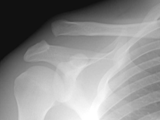

AC Separation

AC Separation